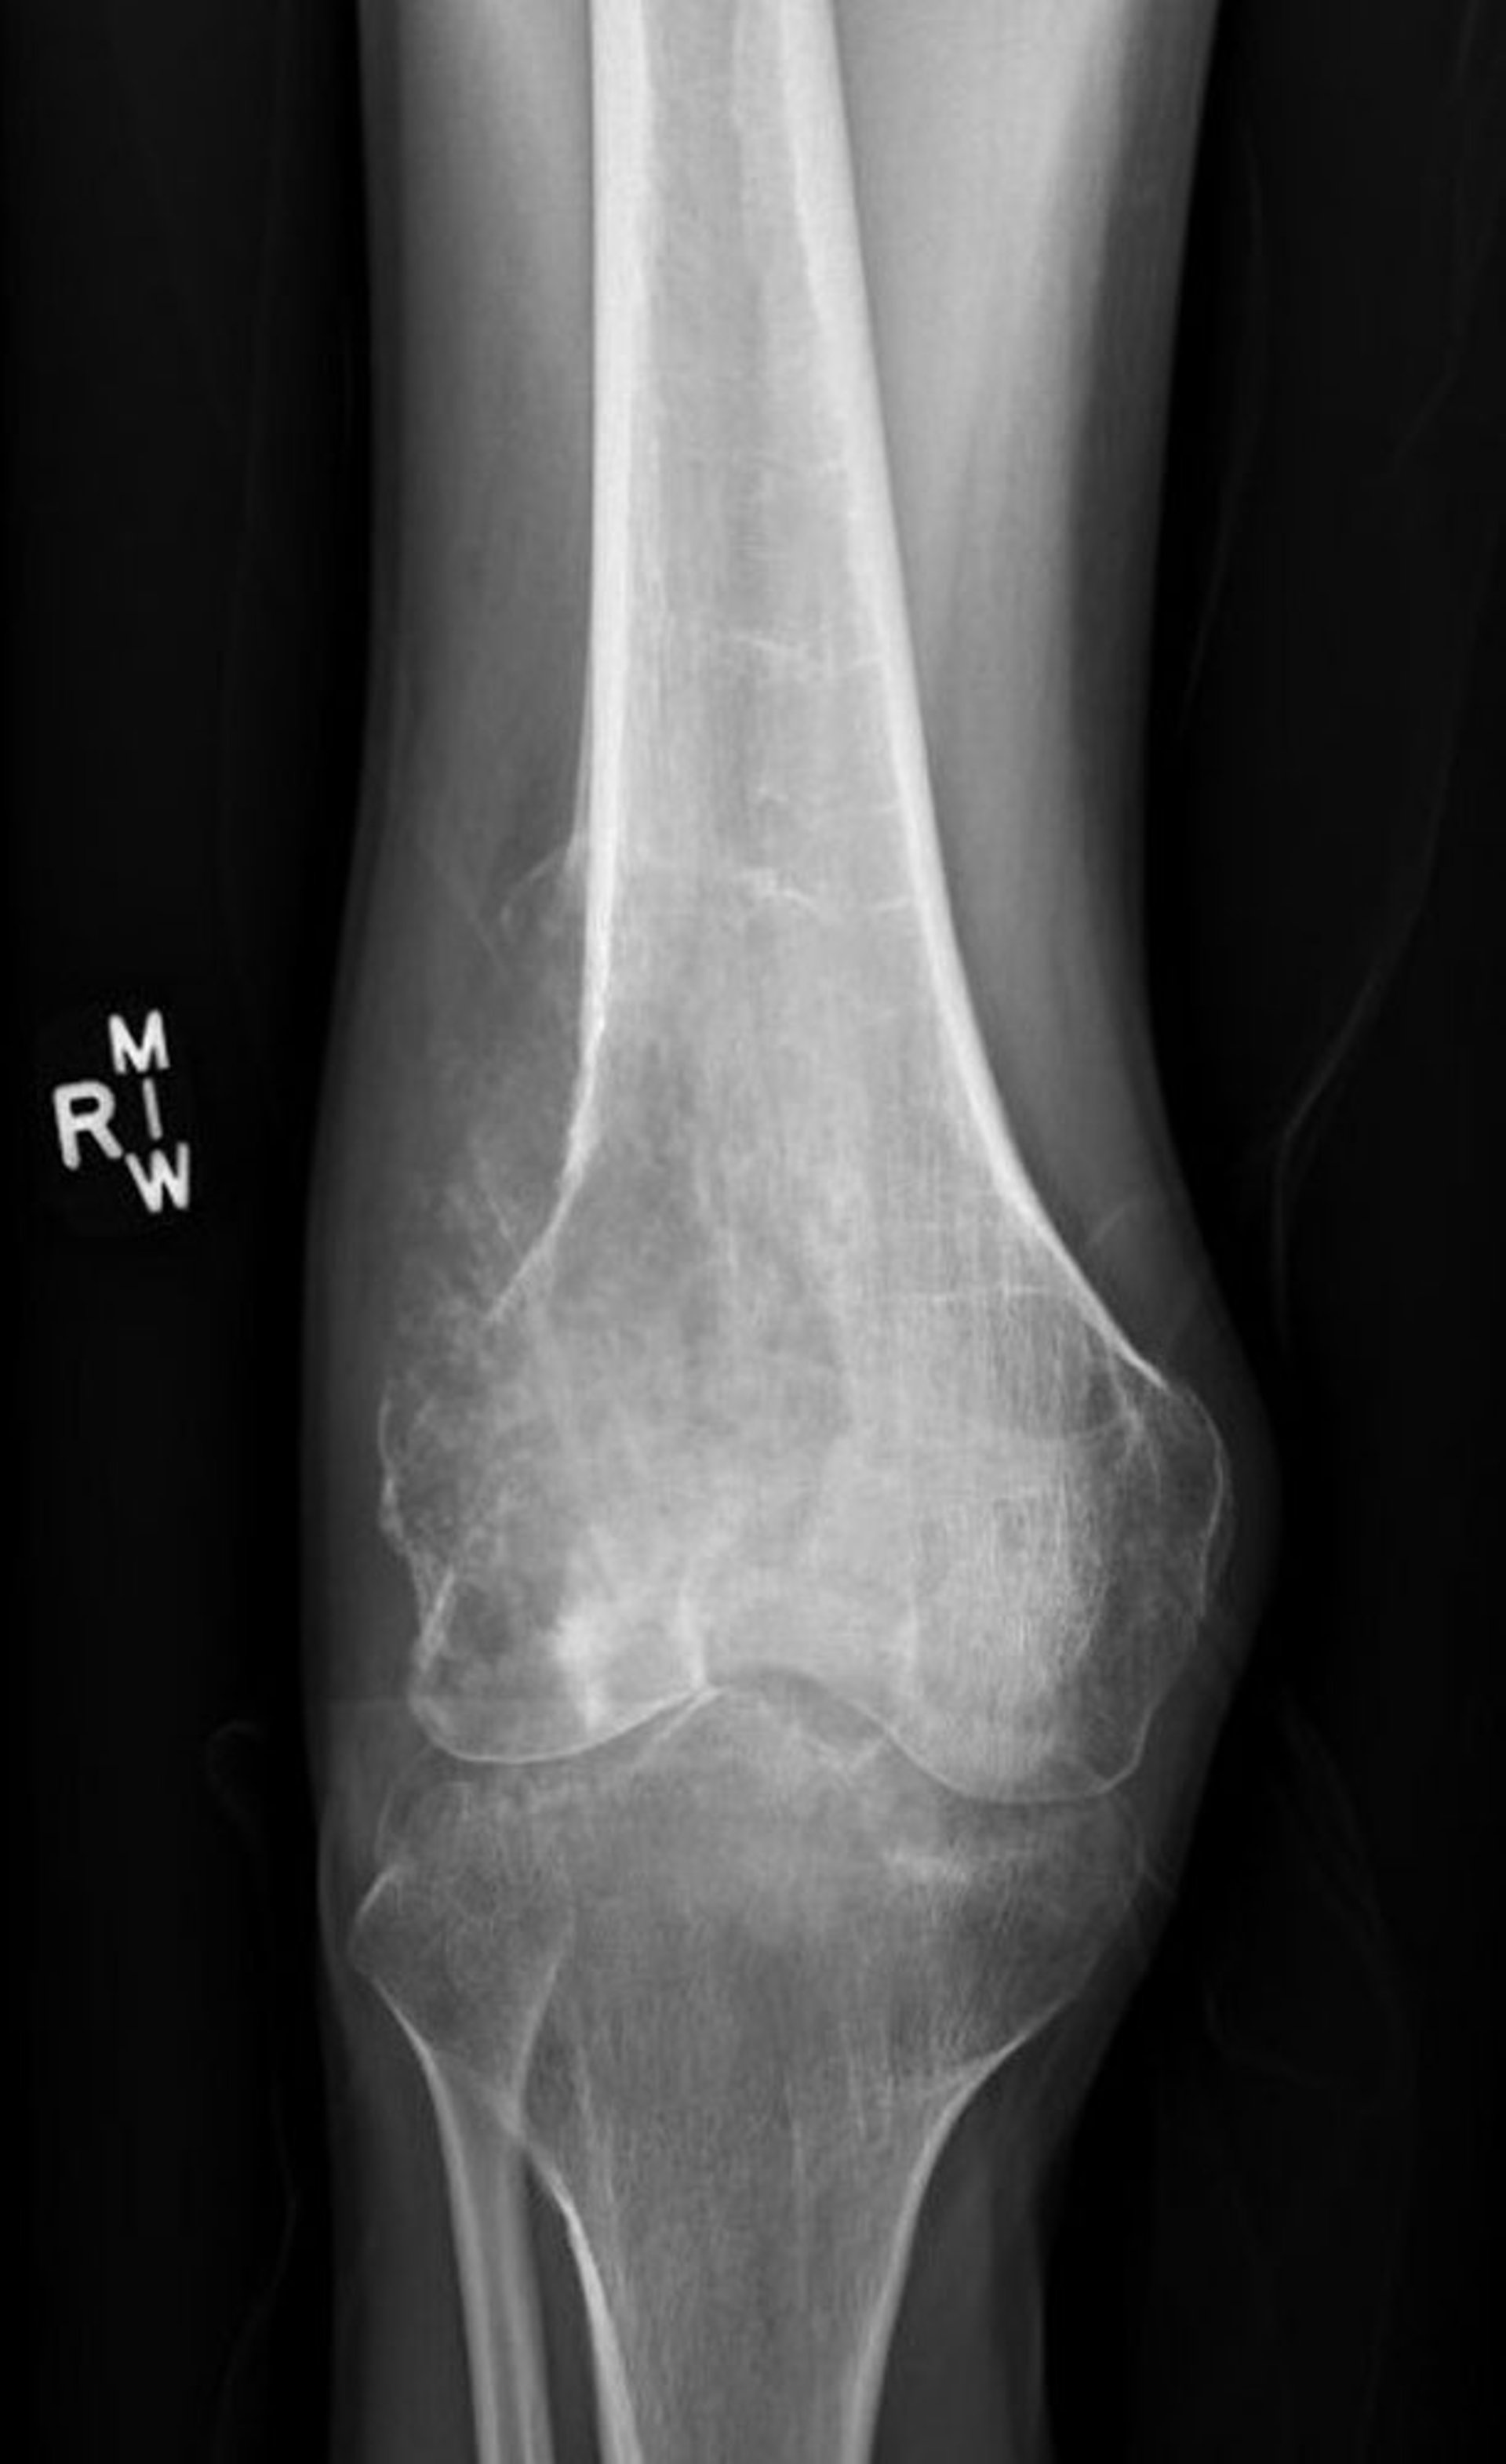

Diese Röntgenaufnahme des Knies zeigt ein destruktives Osteosarkom im Femur oberhalb des Knies mit einem lytischen destruktiven Erscheinungsbild und einem klassischen Codman-Dreieck mit pathologischer Periostanhebung.

Image courtesy of Lukas Nystrom, MD.